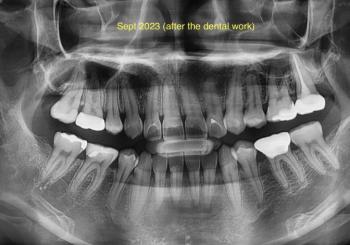

Quick radiographic findings (what I see)

Impacted mandibular third molar(s) (wisdom tooth/teeth) with a mesio-horizontal / mesioangular impaction — the crown is tipped toward the second molar and is at least partially covered by bone/soft tissue.

The impacted crown is in close proximity to the distal surface/roots of the adjacent second molar → this raises risk of decay/resorption of the second molar and increased surgical difficulty.